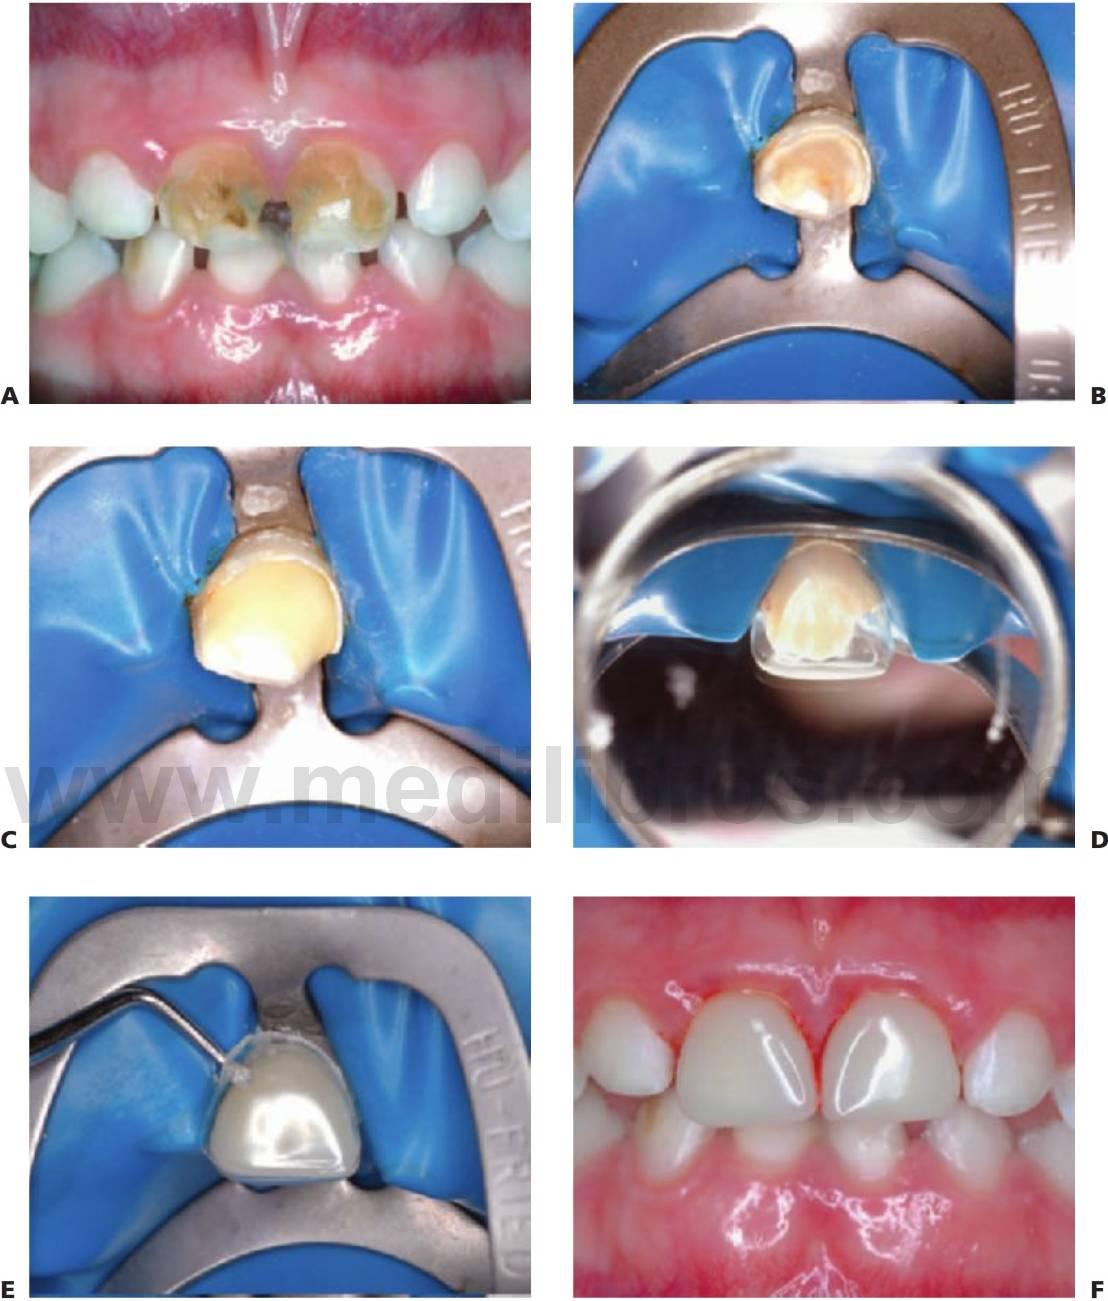

Coronas temporales de resina composite

El composite es el material de elección para la restauración de los dientes temporales anteriores. Una corona temporal anterior con resina composite proporciona una restauración estética y duradera.

Método

- Siempre que sea posible, se debe aplicar anestesia local y aislar con el dique de goma. Por otro lado, debido a la edad y poca cooperación de los niños más pequeños, puede completarse el trabajo restaurador bajo anestesia general.

- Seleccionar la forma de la corona de celulosa adecuada dependiendo de la anchura mesiodistal del diente.

- Eliminar la caries mediante el uso de una fresa redonda a baja velocidad.

- Con una fresa de diamante cónica o una fresa de carburo de tungsteno a alta velocidad, disminuir la altura incisal unos 2 mm, tallar las superficies interproximales y preparar un surco labial en la zona de los tercios gingival y medio de la corona.

- Proteger la dentina expuesta con una base de cemento de ionómero de vidrio.

- Recortar la corona para darle la forma y hacer dos agujeros en los ángulos incisales con un explorador afilado.

- Grabar el esmalte durante 20 segundos, lavar y secar.

- Aplicar una capa delgada de resina adhesiva y polimerizar durante 20 segundos, asegurándose de que todas las superficies están recubiertas homogéneamente.

- Rellenar la corona con un composite de color adecuado y sellar con una presión suave y uniforme, dejando que el exceso salga libremente. El uso de cuñas pequeñas puede ser útil para evitar la aparición de excesos interproximales.

- Fotopolimerizar todas las superficies (labial, incisal y palatina) por igual.

- Retirar suavemente la corona de celulosa, retocar la forma y acabar con fresas de acabado de composite o discos abrasivos.

- Comprobar la oclusión una vez quitado el dique de goma.